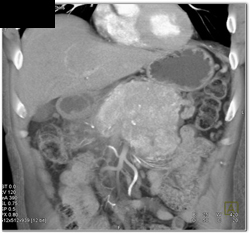

Diagnosis

Islet Cell Tumor